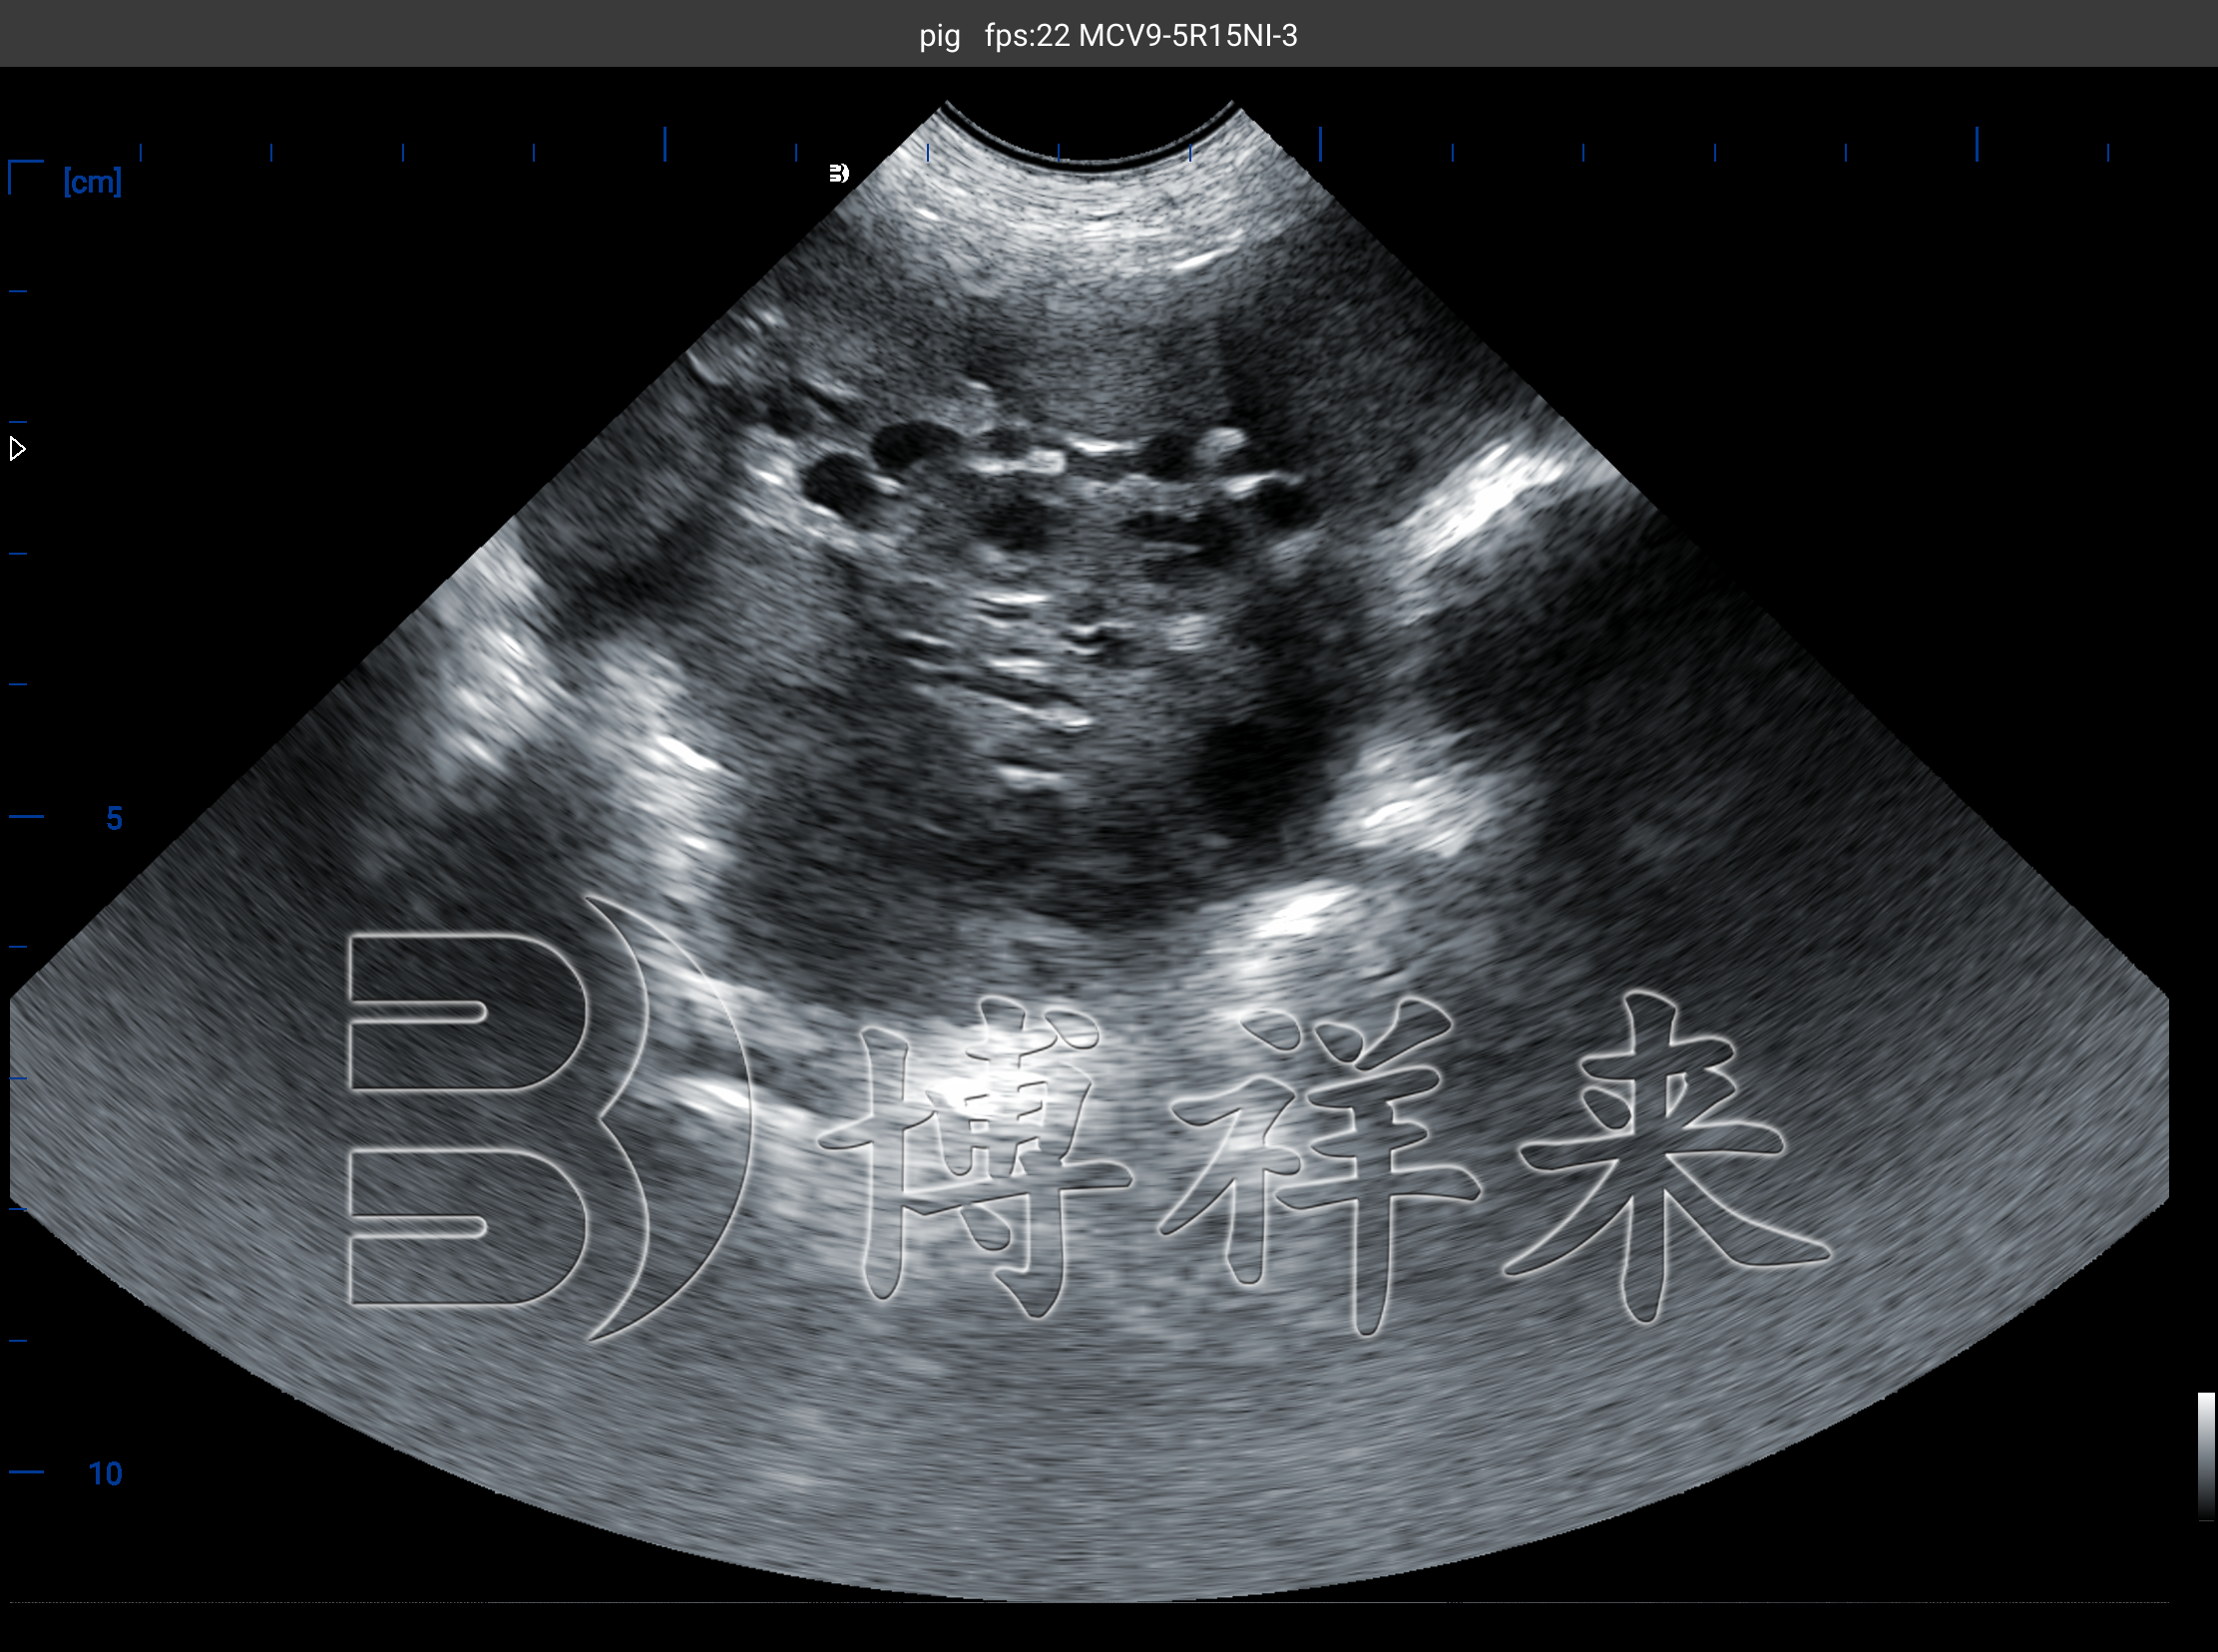

传统的发情鉴定依赖站立反射与外阴变化,但这一方法对管理与人员经验高度敏感。猪用B超机将卵巢与子宫的结构变化直接呈现出来:卵泡、黄体与囊性结构的大小、回声与边界都可被追踪,用于判断发情进程与排卵临近程度。系统性综述明确指出,RTU 已成为评估单头或群体母猪繁殖状态的核心工具之一,适合在商业化猪场的常规流程中应用。

B 超能连续追踪从发情到排卵的卵泡动态,研究在青年母猪与断奶后母猪中均证实可通过超声刻画卵泡生长轨迹与排卵时间窗,显著提升授精时机判断的精度。经典实验与后续研究显示,视觉发情起始后约 7–12 小时是高受胎率时段的重要参考,而超声对“即将排卵”的卵泡群(直径与数量、回声特征)提供了更直观的量化依据。

不仅如此,经直肠超声(TUS)还能通过计数排卵前卵泡与排卵后黄体数量来评估排卵率,为公猪精液用量、授精次数与定时输精(TAI/FTAI)策略提供定量支持,并在发情异常或排卵延迟时提示干预。